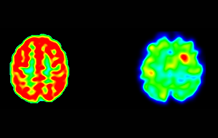

PET scan of a patient with a suspected right pericentral epileptogenic focus. The [18F]DPA-714 PET scan (right) shows a strong and easily perceptible focal increase in uptake in the right precentral zone. Retrospective analysis of [18F]FDG PET (left) reveals sulcal hypometabolism in the region indicated by [18F]DPA-714 PET. (c) Cheval et al., Neurology

In a trial involving 23 people, the BioMaps laboratory (SHFJ), a leader in the use of [18F]DPA-714 in preclinical and clinical studies, has shown that [18F]DPA-714 PET provides more relevant information on the location of epileptogenic foci than [18F]FDG PET. This benefit has made it possible to surgically manage patients who would not have benefited from surgery with the results of FDG PET.

These results indicate that [18F]DPA-714 PET could be an additional tool for the best possible localisation of epileptogenic foci, particularly for patients for whom FDG PET is not informative.​